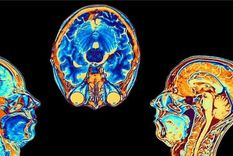

Coronavirus El estudio que muestra cómo cambia el cerebro tras una infección por coronavirus, aunque esta sea leve

test visual En este test visual podrás entender como el cerebro utiliza un complejo entramado de circuitos para leer, ubicados en su mayoría en el hemisferio izquierdo